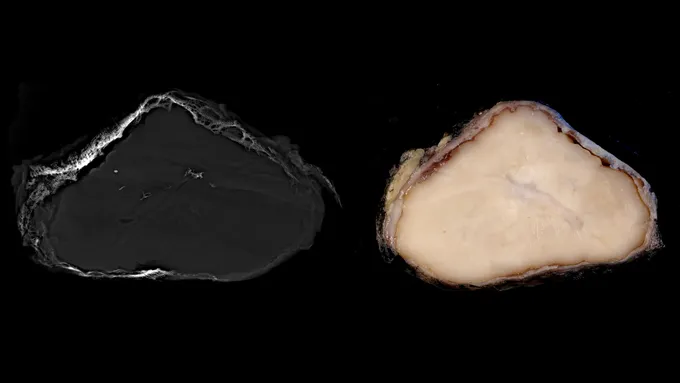

Mais en 2022, le pathologiste John Gross a découvert une tumeur inhabituelle recouverte d'os provenant d'un membre d'un patient. Cela ressemblait au sarcome malin, un type rare de cancer qui représente environ 1 pour cent des cancers chez l'adulte. Il existe des tumeurs établies connues pour avoir des extérieurs osseux. Mais cette masse ne rentrait pas dans une catégorie connue. Par exemple, bien qu’elle contienne de la kératine, une protéine généralement présente dans certaines cellules cancéreuses, l’entité indéfinie ne possédait pas de gènes connus pour être des indicateurs de cancer.

Les chercheurs ont nommé la tumeur OSET (tumeur fusiforme et épithélioïde ossifiante) en raison de son apparence et des deux types de cellules qu'elle contient, toutes deux atypiques dans les tumeurs recouvertes d'os. Cette découverte a permis aux médecins d'effectuer le traitement approprié : retirer la tumeur et éviter la chimiothérapie. Aucun patient de l’étude n’a signalé une résurgence de la croissance depuis l’intervention chirurgicale.